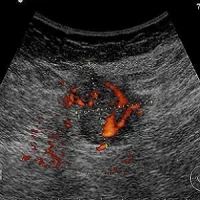

The new scanner builds an image of the tissue by mapping the optical absorption, which is altered by the concentration of haemoglobin – the protein in red blood cells. Regions with higher concentrations of haemoglobin may indicate higher blood floor due to an abnormality such as a tumour.